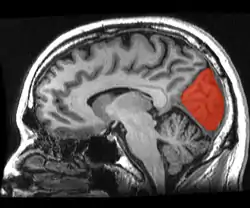

![]() Sagittal MRI slice with the cuneus and lingual gyrus shown in red. | |

The cuneus (Latin for "wedge"; plural, cunei) is a smaller lobe in the occipital lobe of the brain. The cuneus is bounded anteriorly by the parieto-occipital sulcus, inferiorly by the calcarine sulcus.